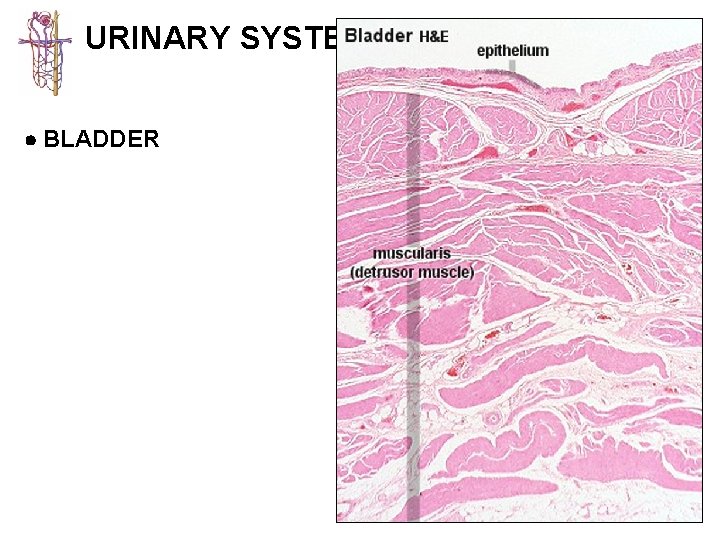

URINARY SYSTEM KIDNEY CALYCES/ URETER BLADDER URETHRA 1 - mucosa lined with transitional 2 -epithelium usually lacking submucosa 3 - muscularis best developed in ureters (2 -3 layers) and bladder (3 layers)

URINARY SYSTEM BLADDER

URINARY SYSTEM BLADDER transitional epithelium